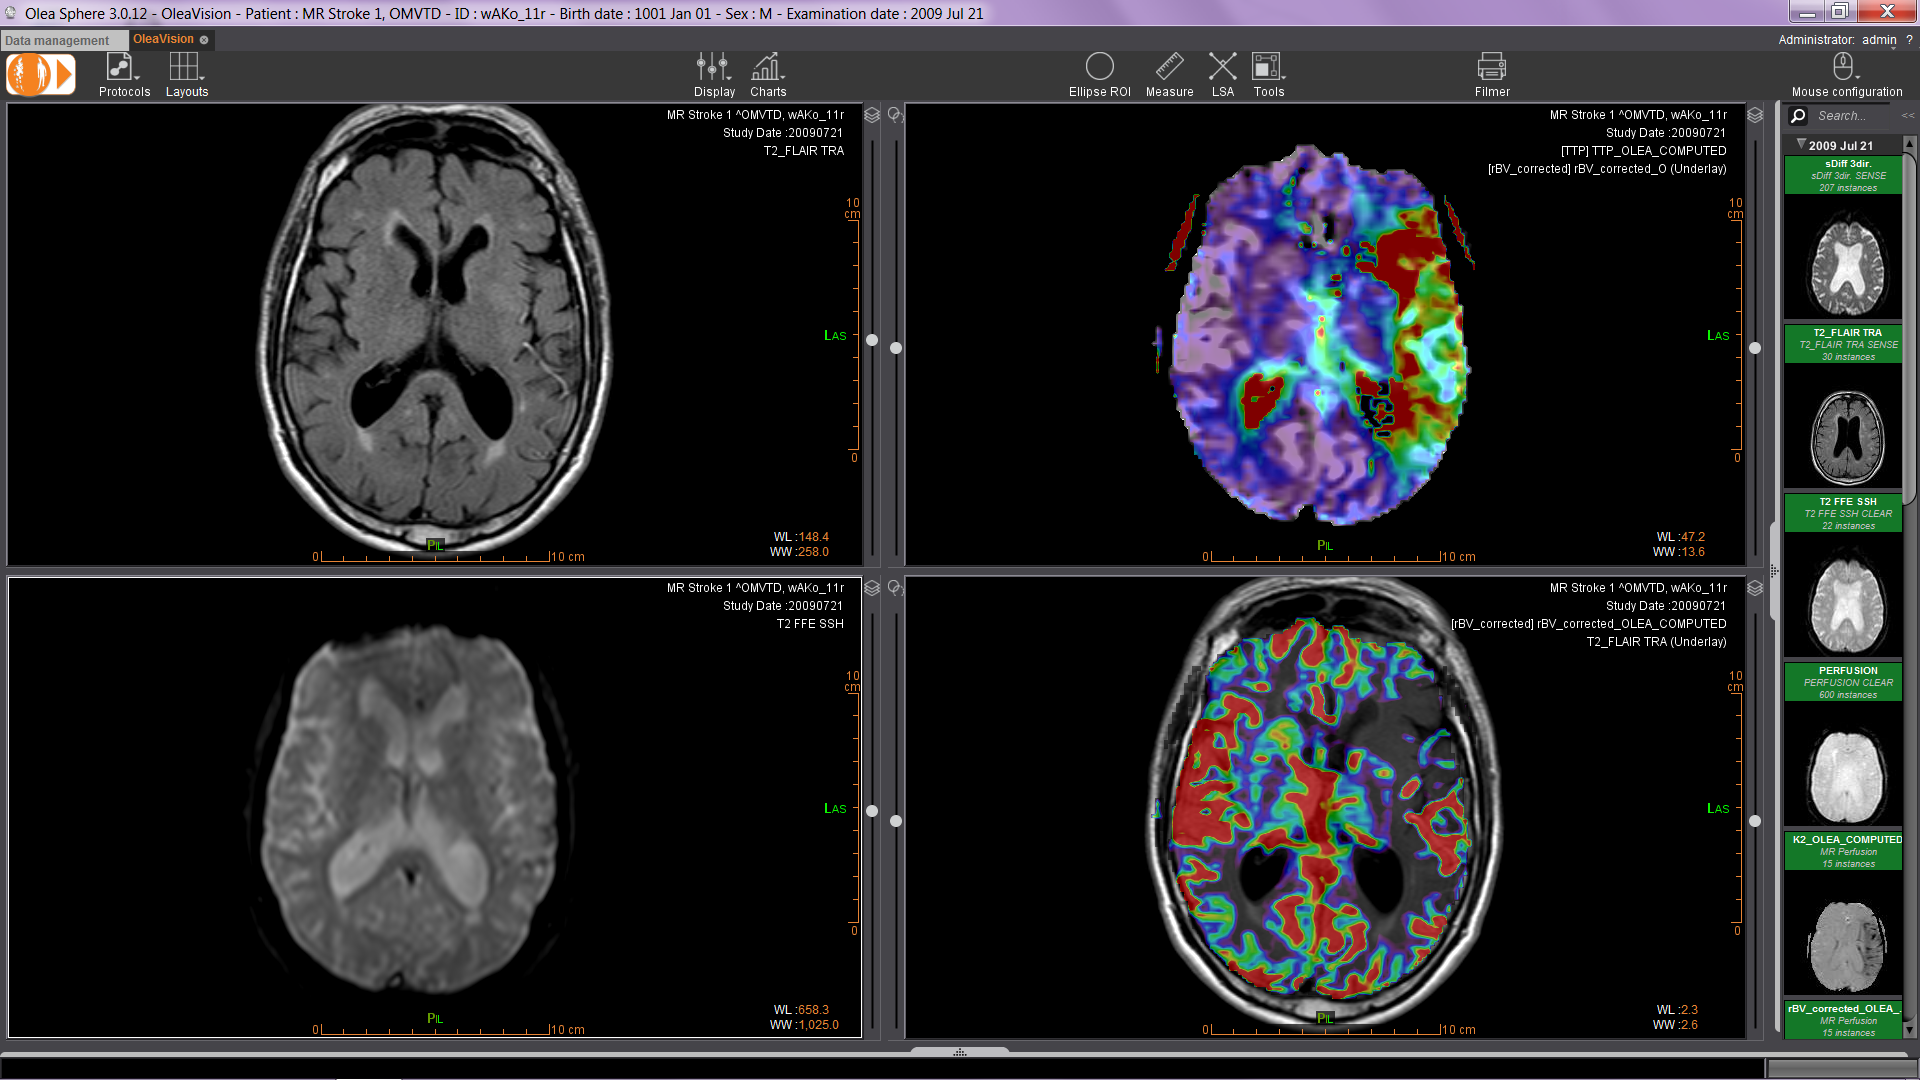

Táto inovatívna spoločnosť sa etablovala ako popredný poskytovateľ pokročilých riešení pre spracovanie obrazu MR a CT, pričom ich najvýznamnejším technologickým úspechom je softvérová platforma Olea Sphere. Ide o vysoko inteligentné a plne automatizované riešenie pre následné spracovanie MRI a CT skenov, ktoré pomáha rádiológom bleskovo a s vysokou mierou istoty vyhodnocovať široké spektrum zložitých patológií. Softvér dokáže zložité surové dáta premeniť na prehľadné, farebne kódované mapy, kvantitatívne analýzy a trojrozmerné modely. Vďaka tomu majú lekári k dispozícii presné merania perfúzie, difúzie či iných kritických tkanivových parametrov, ktoré by voľným okom na štandardných snímkach hľadali len veľmi ťažko.